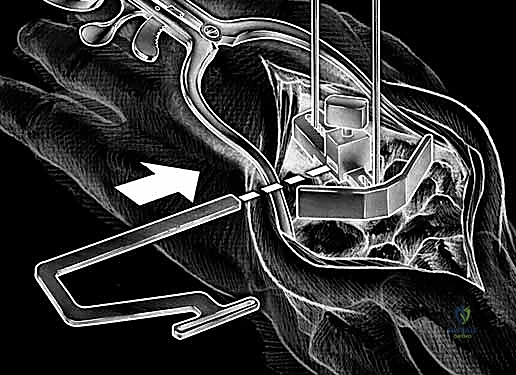

3. الشق الجراحي والوصول للمفصل

يقوم الدكتور هطيف بعمل شق جراحي دقيق في الجزء الخلفي (الظهري) من الرسغ. يتم إبعاد الأوتار والأعصاب بحذر شديد باستخدام أدوات دقيقة لحمايتها من أي ضرر أثناء العملية.

4. إزالة العظام والغضاريف التالفة

باستخدام أدوات جراحية متخصصة، يتم إزالة الصف الأول من عظام الرسغ التالفة، بالإضافة إلى إزالة أطراف عظمة الكعبرة المتآكلة، لتهيئة المساحة لاستقبال المفصل الصناعي الجديد.